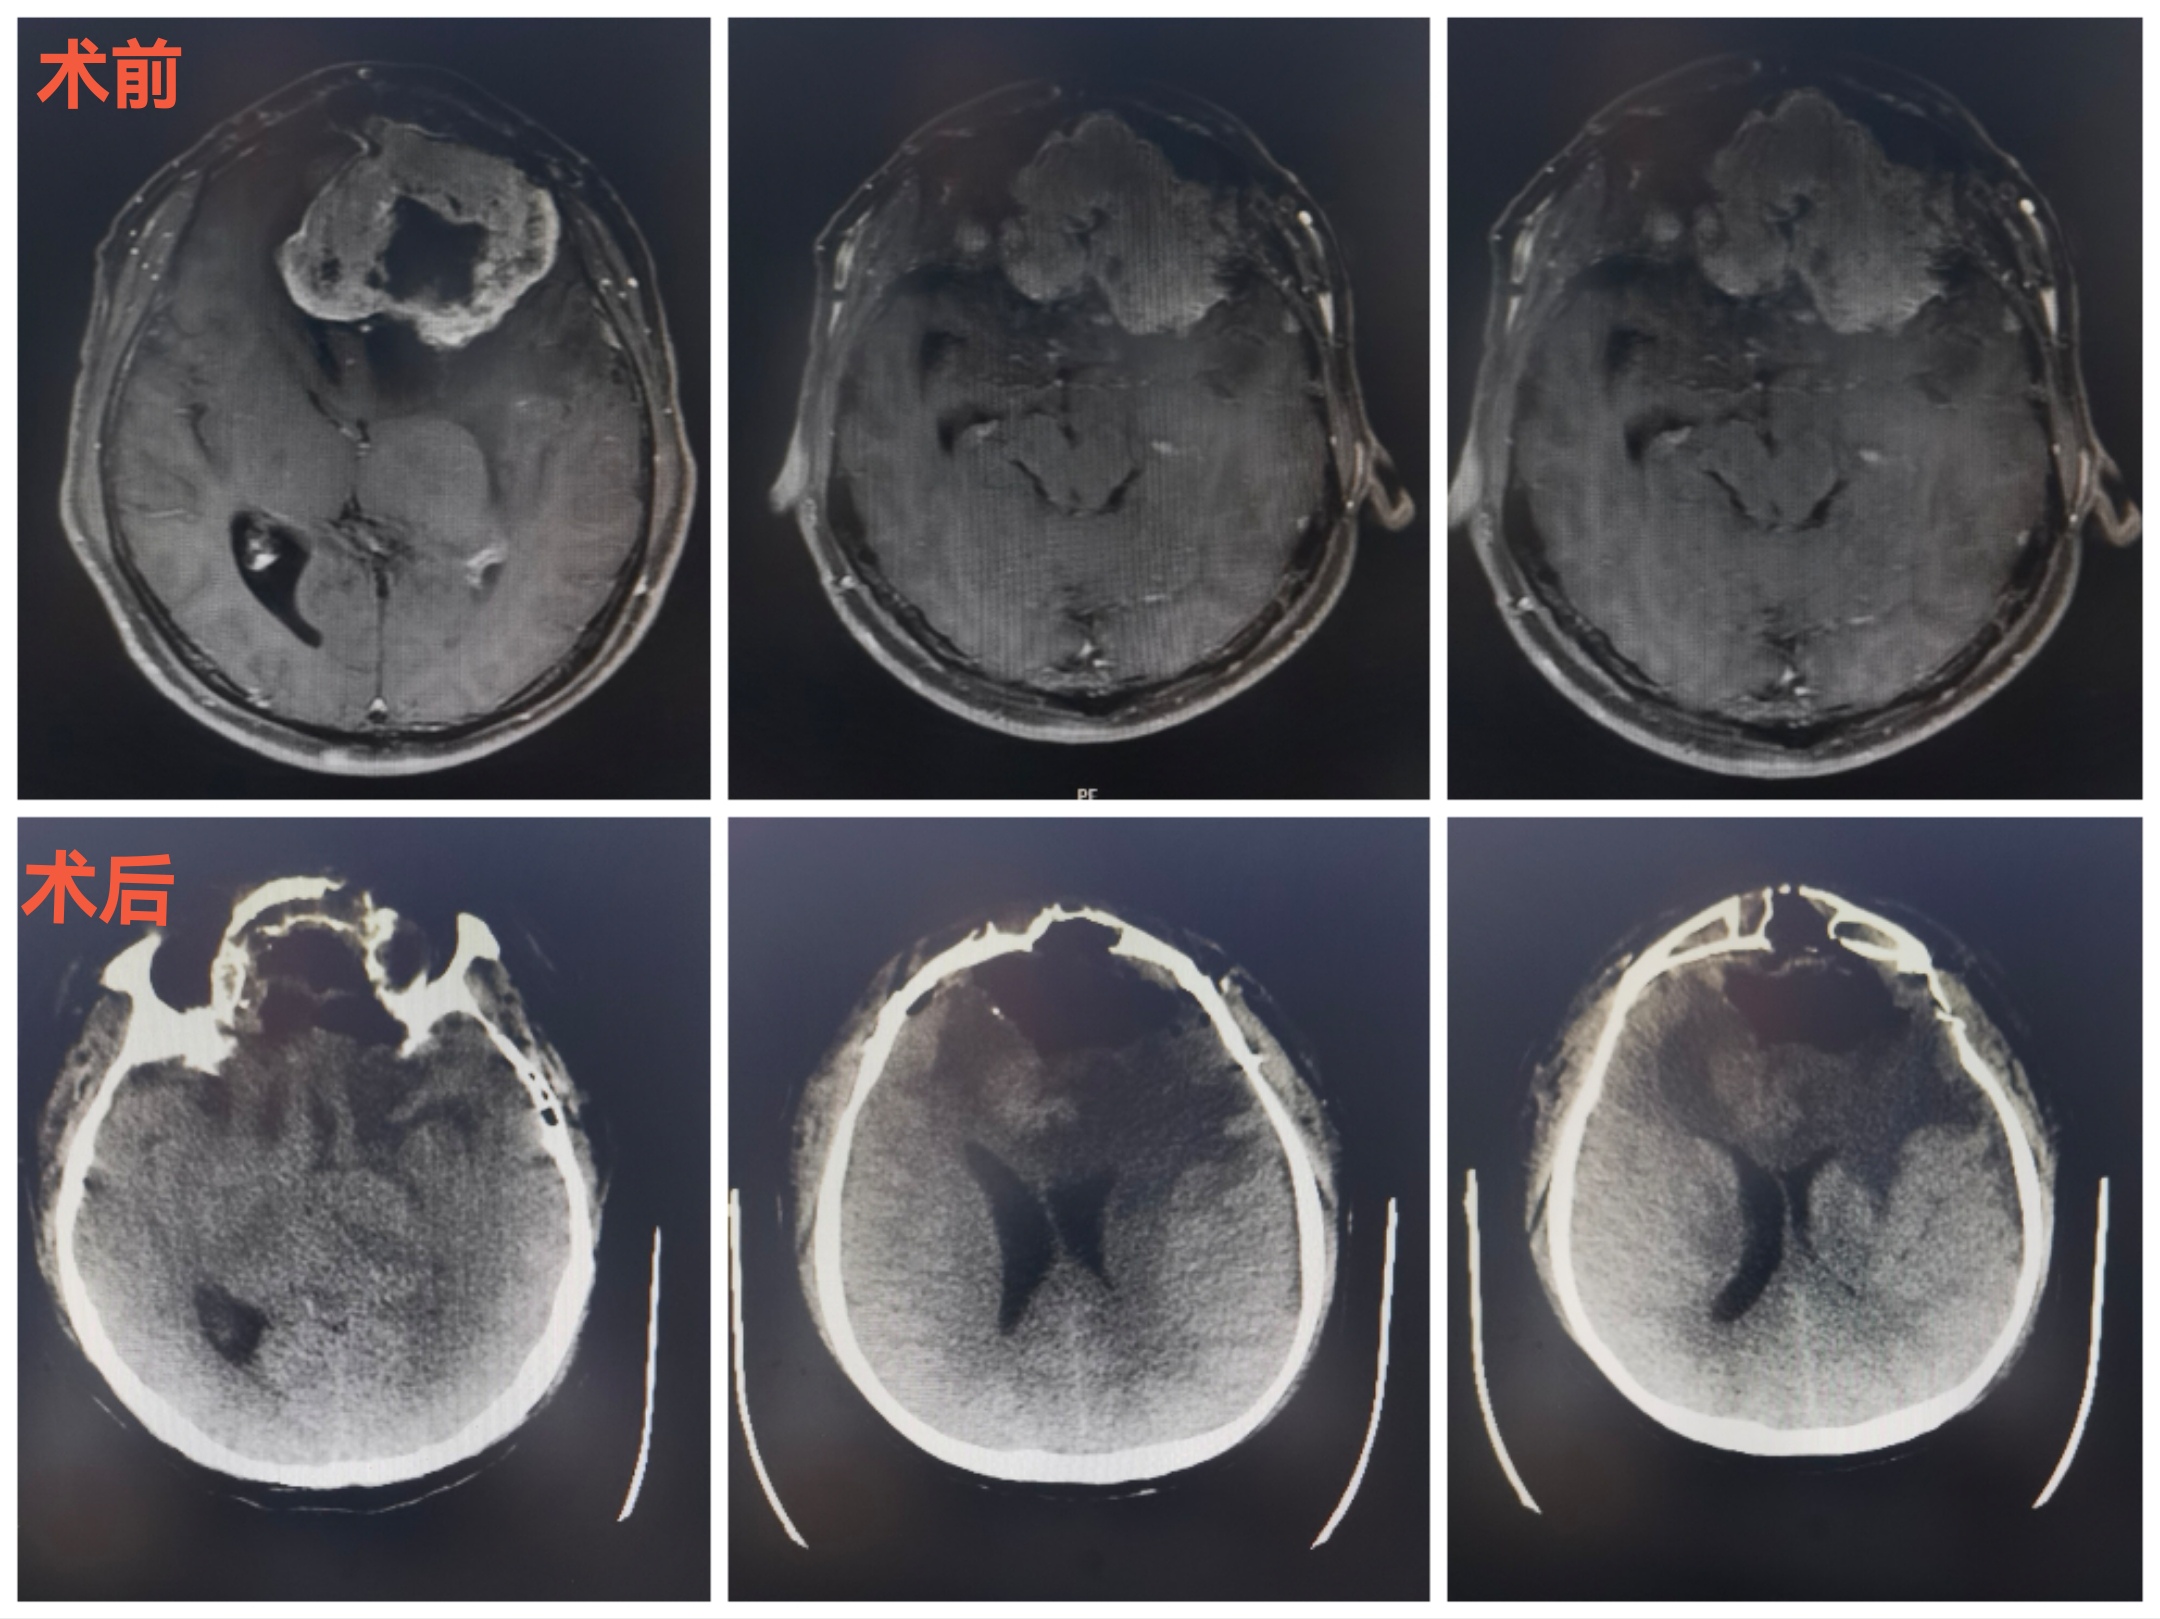

CT扫描可见颅内等密度占位,局部水肿明显,中线向右偏移。冠状位重建可见嗅沟蝶骨平台处骨质破坏导致缺损。

MRI可见肿瘤巨大,中鼻道以上,蝶窦筛窦及双侧额底均为肿瘤组织占据,向两侧到蝶骨嵴。肿瘤分叶状,可明显增强,核心区有坏死。后部可见粗大的静脉。双侧大脑前动脉位于肿瘤的后部。

CT提示颅内肿瘤,前颅底等密度为主。周边水肿明显。占位效应造成中线移位。

CT与增强MRI的对比

术后复查,提示切除理想。颅内的低密度改变为脂肪组织。

术后一个半月,肿瘤切除理想。